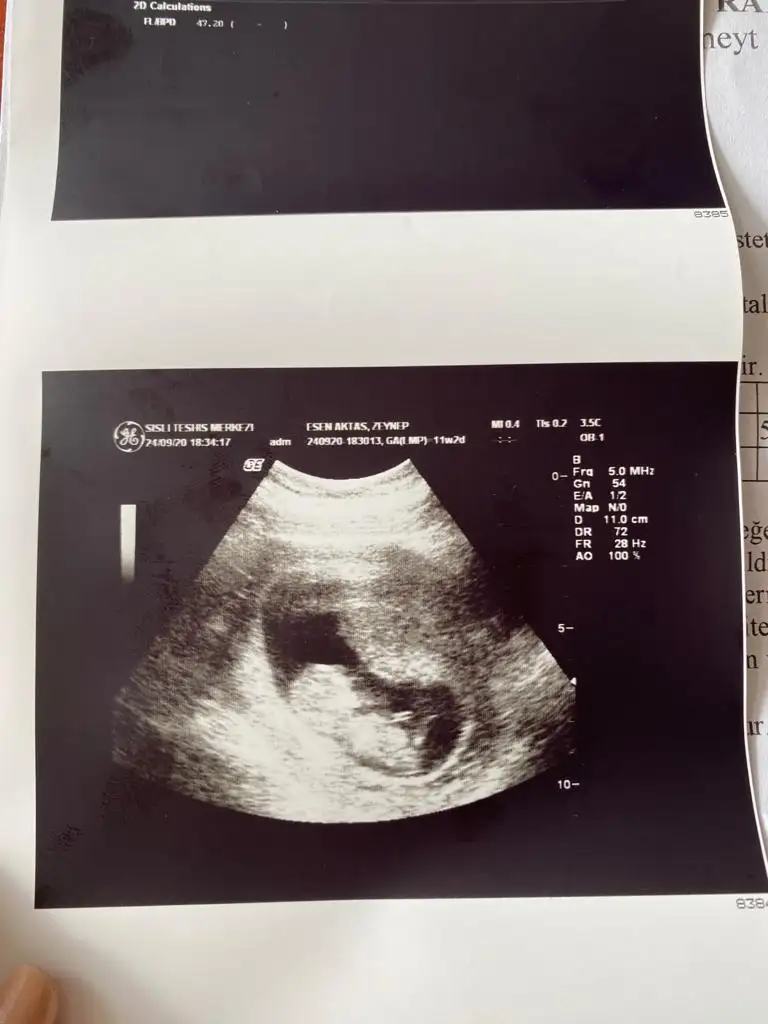

Emin olamadım net değil sanki sanki kız gibi başka USG varsa paylaşın 11 12 13 haftalarBi arkadaşıma ait 15+5 daha öğrenemedi bi tahmin yaparmısınız?

Bu 12.haftaEmin olamadım net değil sanki sanki kız gibi başka USG varsa paylaşın 11 12 13 haftalar

Bu 12.hafta

Sanki kız gibi 12-13 hafta tekrar paylasinMerhaba acaba benımkınde belli mii ben anlayamıyorum